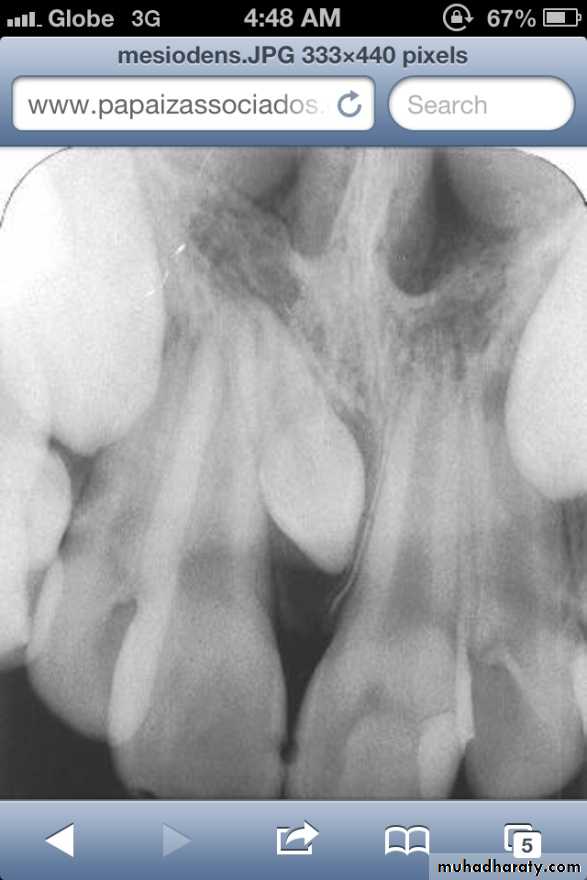

• Mesiodens :When they occur between the maxillary central incisors.

Mesiodens

Many supernumerary teeth never erupt, but they may delay eruption of nearby teeth or cause other dental problems.